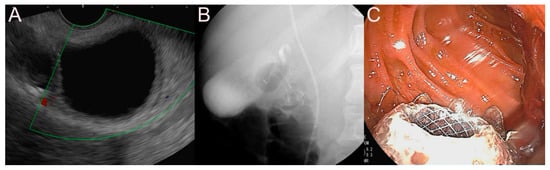

2.3. Stent for EUS-Guided Gallbladder (GB) Drainage

2.3.1. Use of the Plastic Stent

2.3.2. Use of the SEMS

2.3.3. Use of the LAMS